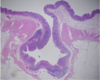

Ischemic Enteritis

Ischemic Enteritis

Ischemic Enteritis

Ischemic Enteritis